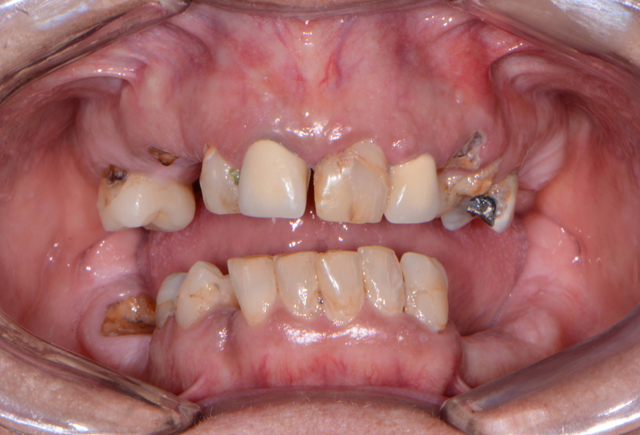

A patient presented to my practice for a consultation, wanting to restore her dentition to proper form and function. She complained of generalized discomfort in these teeth due to the gross caries and periodontal disease that were readily apparent (Fig. 1). There were several teeth in both arches that were already removed due to gross decay and/or periodontal disease.

Fig. 1 Fig. 2